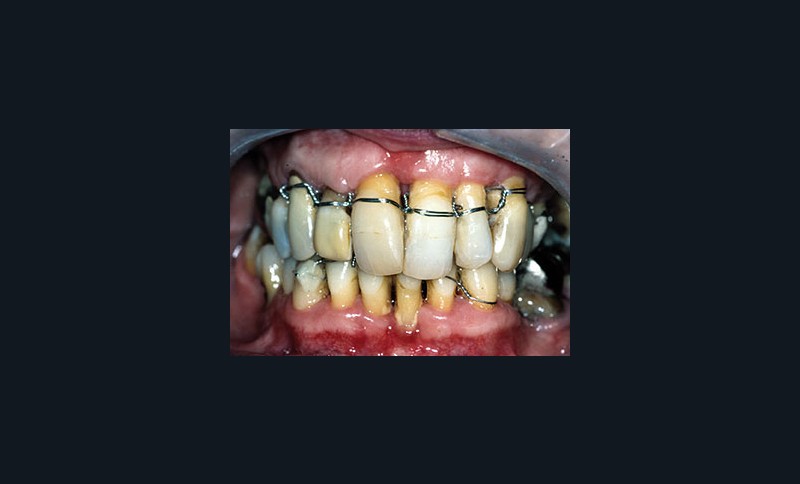

Une patiente âgée de 45 ans consulte à la fin des années 1990 avec une contention en échelle au maxillaire afin de soulager les mobilités des dents antérieures.

Les examens cliniques et radiographiques montrent une parodontite chronique généralisée (fig. 1a à m).

La patiente, en bonne santé, ne fume pas.